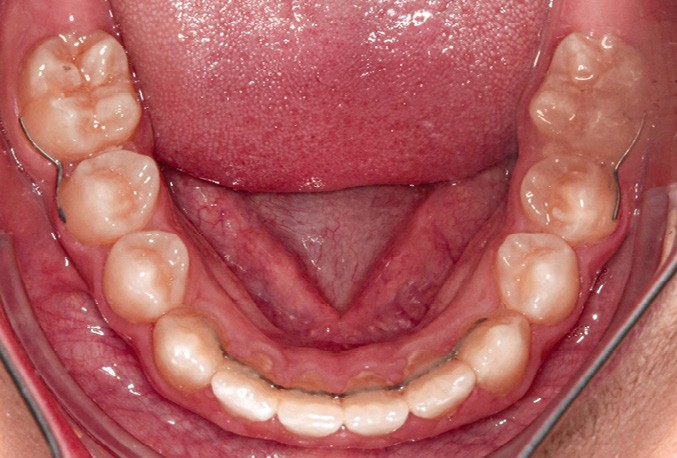

En complément des fils de contention 3-3 bimaxillaires, des contentions (fils collés acier 0.16 x0.22) ont été réalisées entre 15-17, 25-27, 35-37 et 45-47. L’objectif était d’éviter une réouverture des espaces post mésialisation.

Une sur-correction de la rotation de 17 aurait été souhaitable pour optimiser l’alignement et les rapports occlusaux (fig. 2a-d).